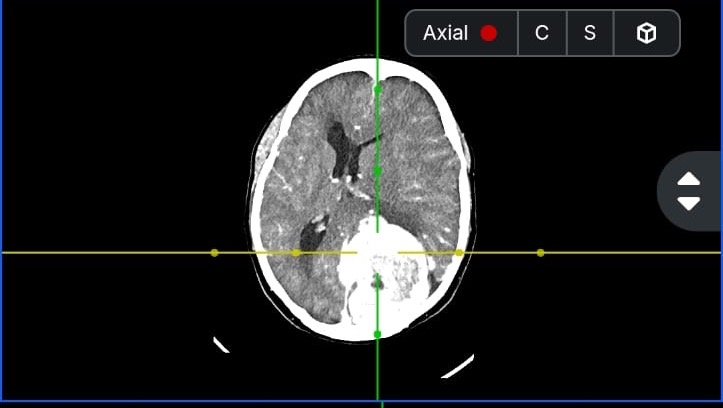

Hola me llamo Lucia del Carmen Morales Auvert tengo 38 años y estoy recaudando fondos ya que tengo que ser intervenida de emergencia debido a un proceso expansivo intracerebral y no cuento con los recursos necesarios para cubrir dicha operación, a su vez tengo que realizarme una Angiografia, gastos médicos y gastos quirúrgicos.

En este momento me van a realizar una embolizacion. Es un procedimiento para tratar vasos sanguíneos anormales en el cerebro y otras partes del cuerpo. Este procedimiento interrumpe el riego sanguíneo a cierta parte del cuerpo. Para después realizar la cirugía